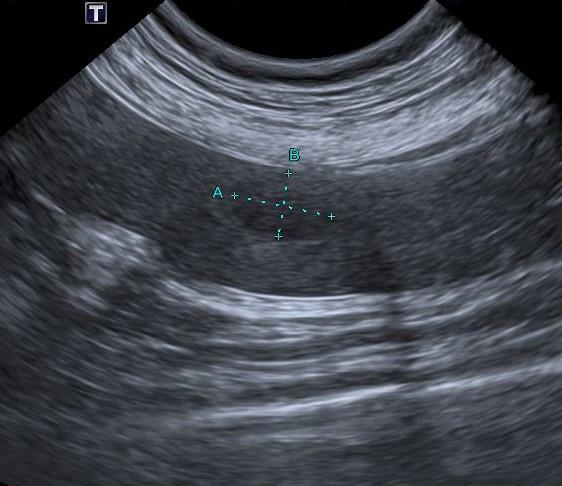

Se realiza ecocardiografía en la cual observamos engrosamiento de la válvula mitral (Fig. 2) y alteración de la estructura de las cámaras cardiacas: ratio atrio izquierdo/aorta 2,25 (Fig. 3), diámetro de ventrículo izquierdo en diástole normalizado (DVIdn) 1,98, patrón de flujo transmitral pseudonormal con velocidad máxima de onda E de 1,7 m/s, tiempo de relajación

isovolumétrica (TRIV) acortado, 30 ms, y regurgitación mitral de hasta 4,6 m/s. En la ecocardiografía se observa también una masa hiperecoica bien definida de hasta 7 x 4,3 cm de diámetro en la base aórtica (Fig. 4) y un acúmulo de derrame pericárdico leve que no permite la pericardiocentesis. Además, se detecta un nódulo hiperecoico redondeado de 1,56 cm de diámetro en la válvula tricúspide (Fig. 5).

Figura 2. Ecocardiografía en corte paraesternal izquierdo eje largo, de 4 cámaras en la que se observa engrosamiento de la válvula mitral (flecha). Figura 3. Ecocardiografía en corte paraesternal derecho eje corto en base de corazón, visualizando ratio atrio izquierdo/aorta aumentado. Figura 4. Ecocardiografía en corte paraesternal izquierdo en base de corazón, en las que se observa la estructura hiperecoica y heterogénea junto a la aorta en un corte de la lesión transversal (A) y otro longitudinal (B). Compatible con neoplasia. A B Figura 5. Ecocardiografía en corte paraesternal izquierdo eje largo, optimizada para válvula tricúspide en la que se observa estructura hiperecoica.

La ecocardiografía es el método de elección para confirmar el diagnóstico de EDVM y estimar la severidad de la regurgitación mitral. Los hallazgos ecocardiográficos incluyen el engrosamiento y/o prolapso de las hojas mitrales junto con la identificación de la regurgitación mediante Doppler. Como se comprobó en el estudio post mortem en nuestro caso, a menudo se observan alteraciones en la válvula tricúspide, pero suelen ser menos marcadas que las de la válvula mitral.2 La ecocardiografía permite adquirir dimensiones del AI en relación con la aorta, o valoración del diámetro del VI en diástole y sístole, muy útiles para estimar el grado de remodelación (agrandamiento) cardíaco.2